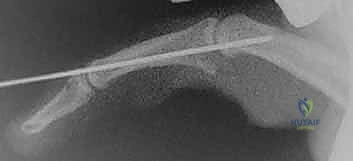

الخطوة 6: التثبيت المؤقت (اختياري)

في بعض الأحيان، ولضمان التئام الصفيحة في مكانها الجديد دون إجهاد، قد يقوم الدكتور هطيف بتمرير مسمار معدني رفيع (K-wire) عبر المفصل لتثبيته في وضعية ثني خفيفة (حوالي 20 إلى 30 درجة) لمدة أسبوعين إلى ثلاثة أسابيع.